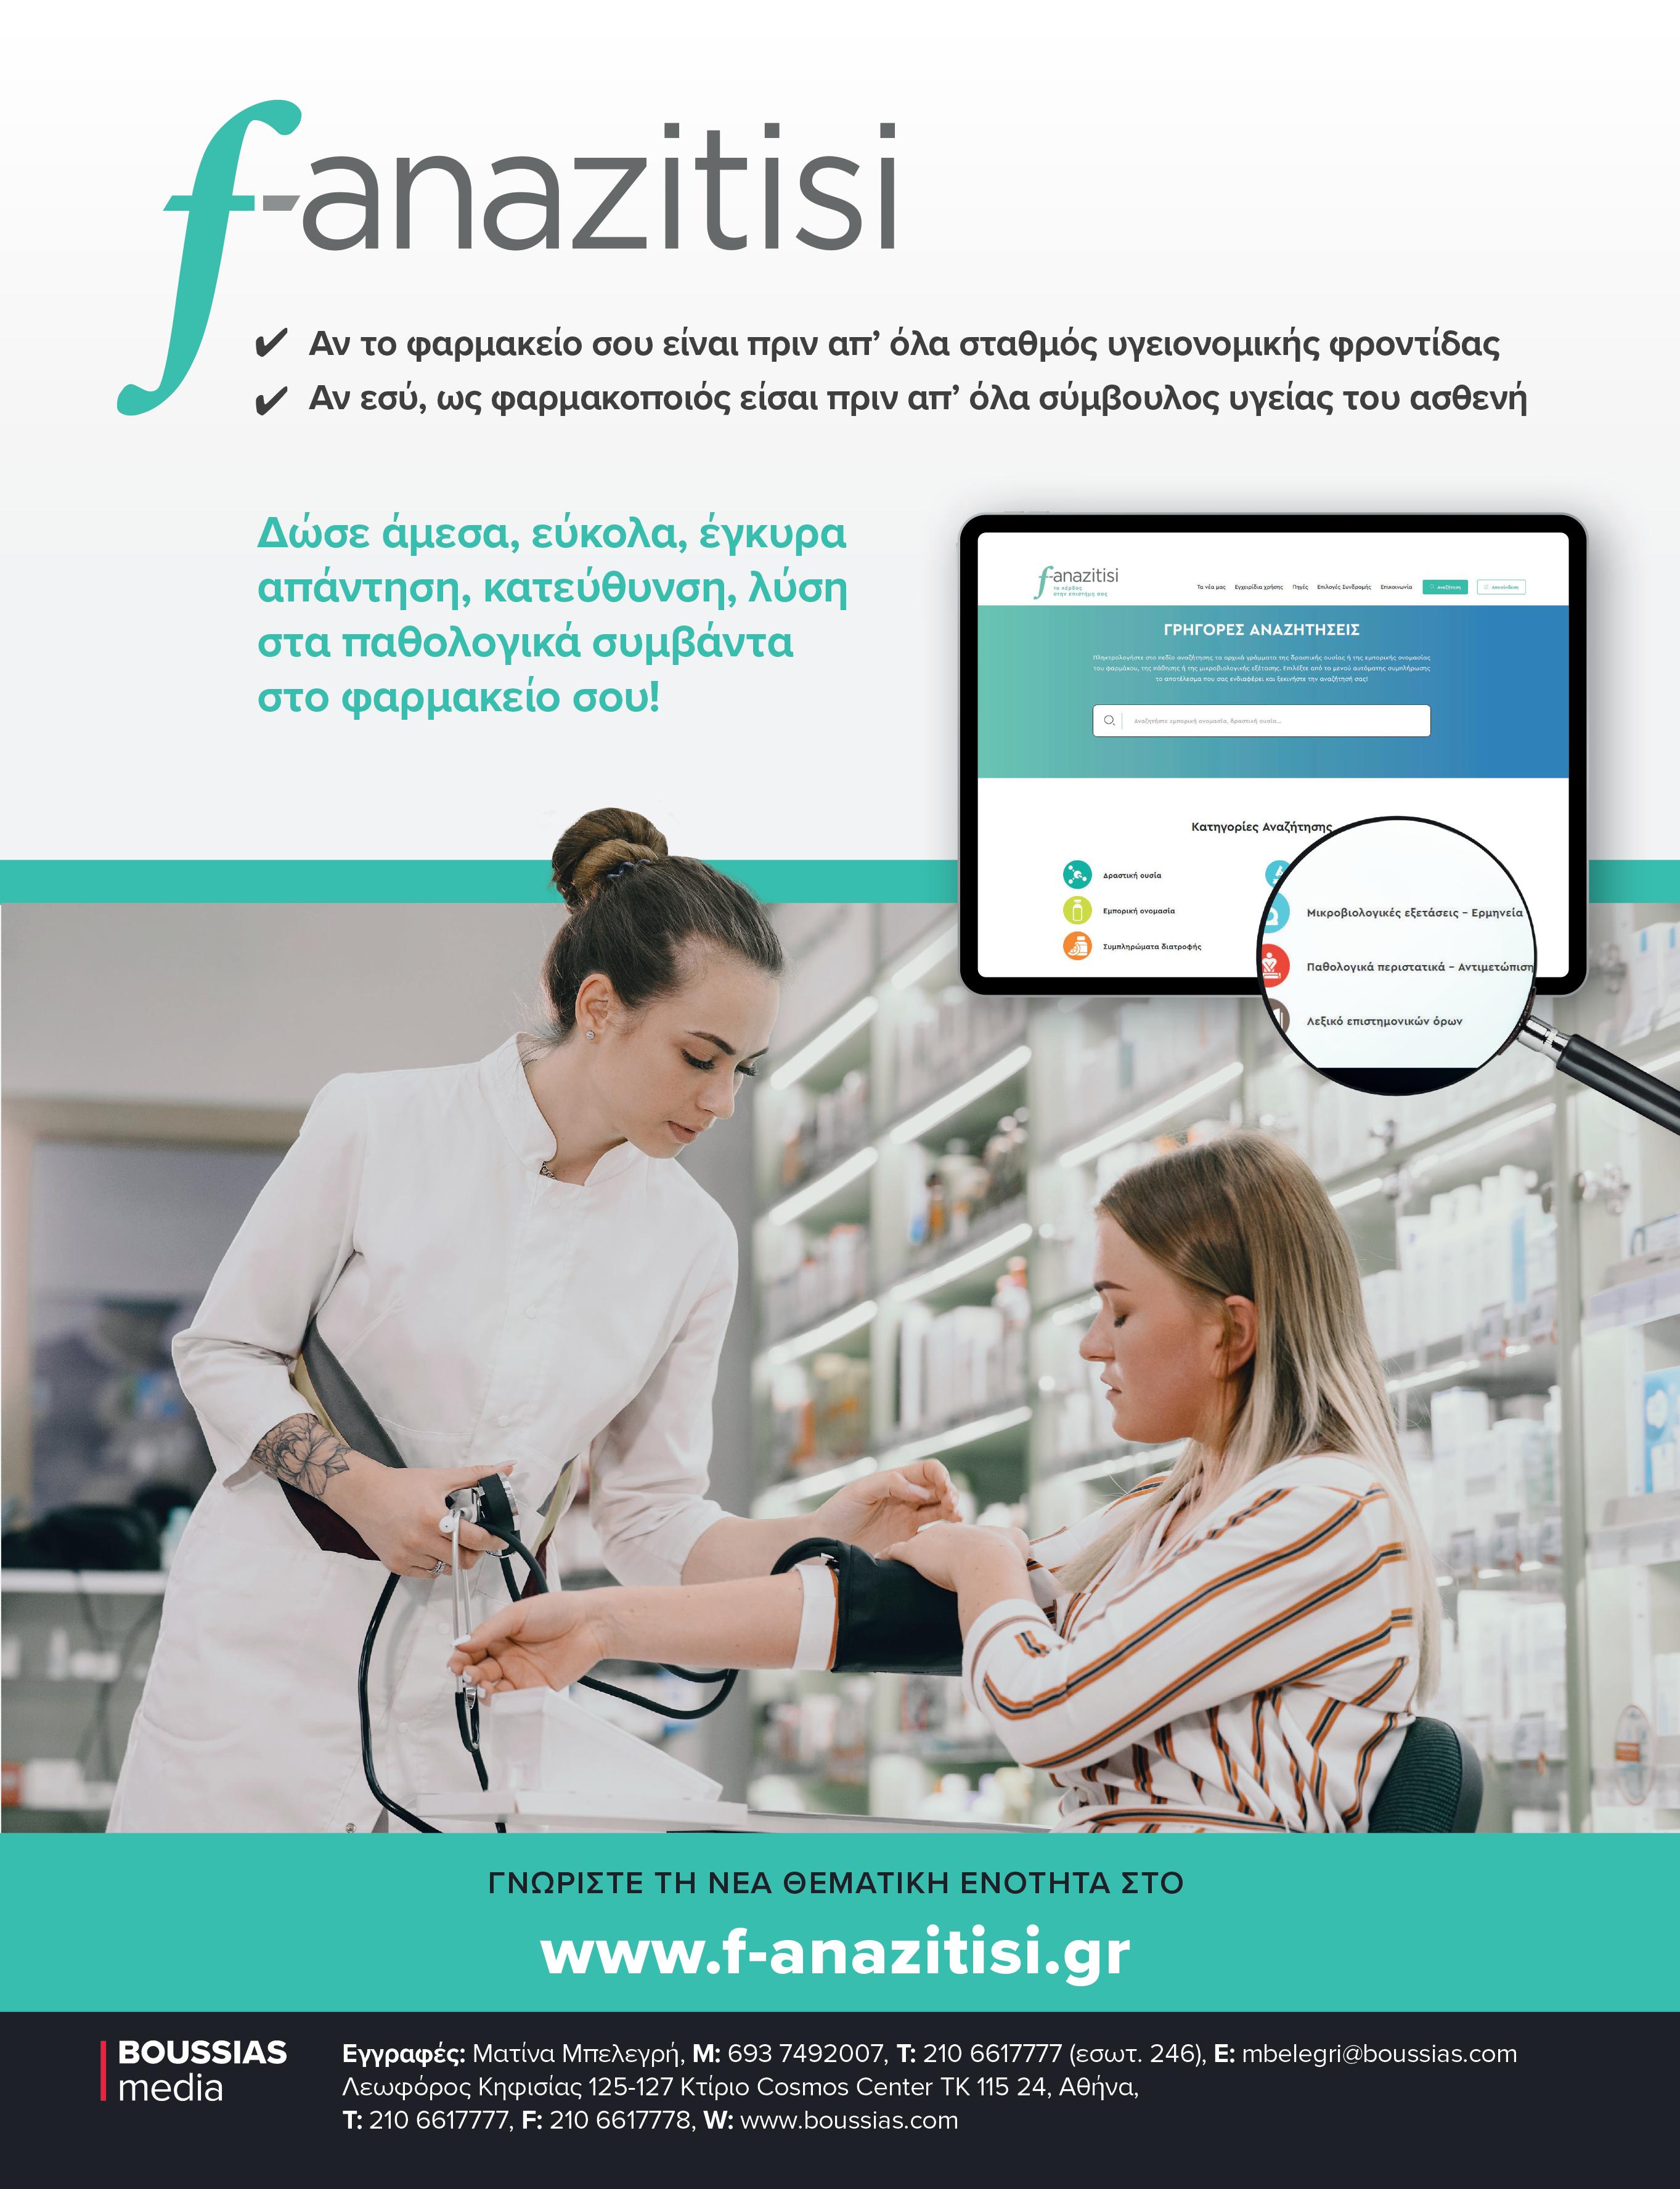

Φαρμακοποιός,

Ενδυναμώνοντας